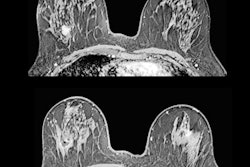

Percentage of images scored as perfect, good, moderate, and inadequate by Volpara PGMI for original views, repeat views, and accepted views.

A significant (p < 0.001) reduction in inadequate scores was observed between the original (41%) versus repeat views (9%) of the technical repeat studies.

Distributions across the Volpara PGMI categories varied between the original views that were subsequently repeated and accepted images, with significantly fewer perfect (2% vs. 17%, p < 0.001) and more inadequate (41% vs. 2%, p < 0.001) scores in the original versus accepted groups, respectively.